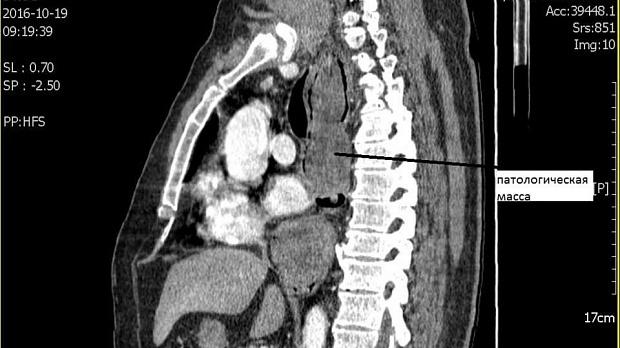

Дословного описания КТ под рукой сейчас нет основной смысл такой: патологическое образование в просвете пищевода длиной до 30 см и толщиной в своей самой толстой части до 6 см. Исходит похоже из задней стенки пищевода т.к. на большем протяжении остальной части образования можно проследить сепарацию от стенок пищевода. Пищевод сильно растянут. Образование солидное. литое. с некоторой неоднородностью. видны небольшие сосуды. Плотность может соответствовать лейомиоме. За пределы пищевода не выходит.